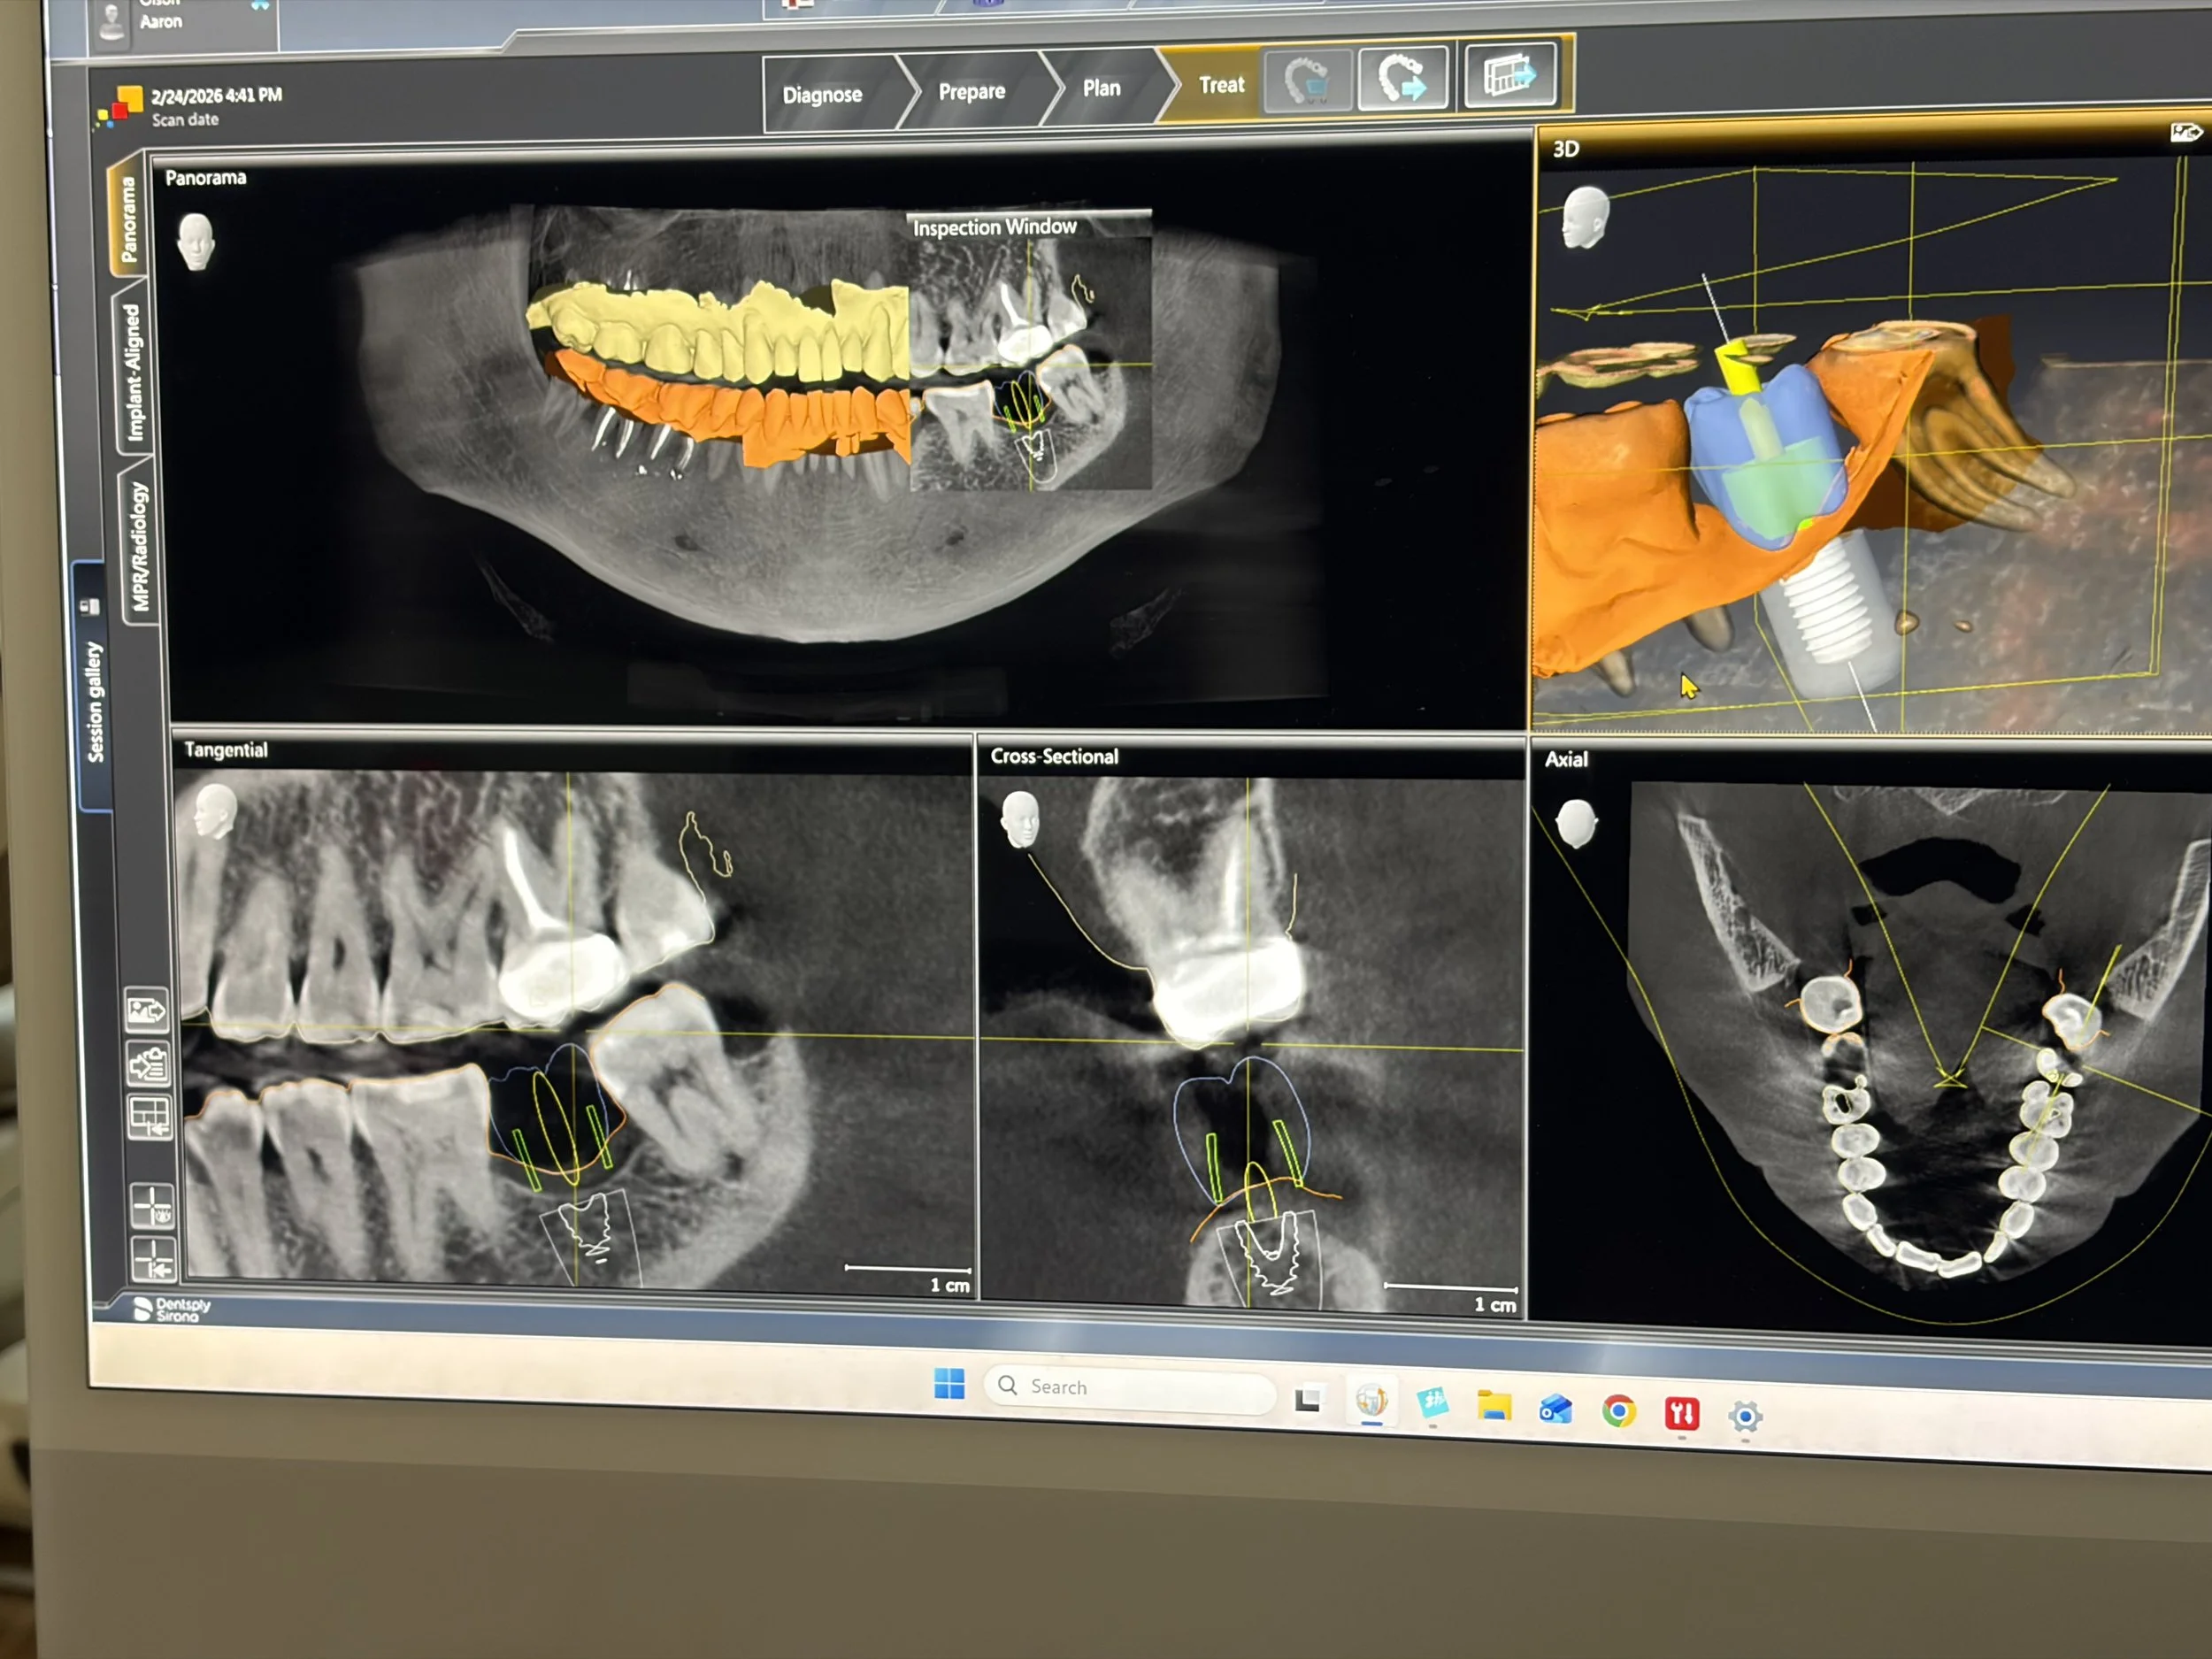

Dr. Weber welcomed the group warmly and shared how dentists help people care for their teeth and protect their smiles. The learners gathered around a large monitor where he showed them detailed dental scans and X rays of teeth and jaw structures. The children watched closely as Dr. Weber explained what dentists look for when examining teeth and how these images help them understand what is happening inside the mouth.

The learners were especially fascinated by the advanced technology used in the office. Dr. Weber showed them digital scans that reveal how teeth come together when we bite and chew. On one screen, colorful markings highlighted the pressure points where teeth meet. Seeing these images helped the children understand how dentists study the way our mouths move and function.

Dr. Weber also introduced the learners to some of the tools and technology used to repair and restore teeth. They were able to see the many small components used in dental implants and how dentists carefully select and place these pieces to help rebuild a patient’s smile. The children were amazed by the precision involved and by the number of specialized tools used in modern dentistry.